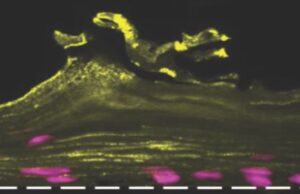

Ο γυναικείος κόλπος έγινε… τσιπάκι από επιστήμονες του Χάρβαρντ

Την τελευταία δεκαετία, ο Δρ. Ντον Ίνγκμπερ, βιομηχανικός στο Πανεπιστήμιο Χάρβαρντ, έχει κατασκευάσει περισσότερα από 15 τσιπ που μοιάζουν και λειτουργούν όπως τα ανθρώπινα όργανα, πνεύμονες, συκώτι,...